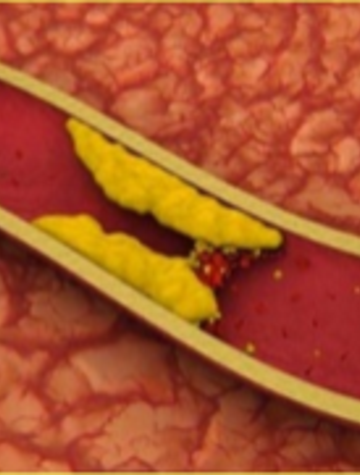

Hypercholestérolémie familiale : diagnostic, prise en charge, dépistage

L’hypercholestérolémie familiale (HF) est une maladie héréditaire autosomique dominante, caractérisée par une élévation du LDL-Cholestérol plasmatique (LDL-C) à l’origine d’une athérosclérose et d’une insuffisance coronarienne prématurées(1-3). Les formes homozygotes sont très rares et ont dès l’enfance un pronostic sévère nécessitant une prise en charge en milieu spécialisé. À l’état hétérozygote, il s’agit en revanche d’une affection fréquente, cliniquement silencieuse [...]